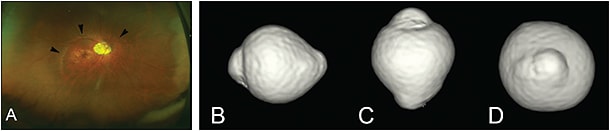

Staphyloma also can occur in eyes that do not have long axial length. Curtin1 showed that in eyes with type I staphyloma, the most common type, the axial length ranged from 25 mm to 38 mm. He therefore emphasized that axial length was not a reliable marker to define pathologic myopia, and he concluded that pathologic myopia should be defined by the presence of staphyloma. Wang et al6 recently reported clinical features of staphylomas in eyes whose axial lengths measured fewer than 26.5 mm. Thus, outpouching of the wall of eyes without long axial length is also considered to be posterior staphyloma (Figure 1D).

The most common methods to detect staphylomas have been color fundus photography and ultrasonography. Especially, conventional 50° fundus photos are widely used in many epidemiological studies. However, most staphylomas involve wide areas of the fundus (especially the upper and temporal direction), and thus the entire extent of the staphyloma does not fit within the 50° field of view of conventional fundus photographs (Figure 2). Similarly, in most cases, staphylomas are too wide to fit into the length of an OCT scan (Figure 3).

Based on stereoscopic fundus observations, Curtin1 classified posterior staphylomas in eyes with pathologic myopia into 10 types (Figure 6). Types I to V were considered primary staphylomas and types VI to X were combined staphylomas. This is the most frequently used classification; however, it is determined from ophthalmoscopic appearances, which might be rather subjective.

Among staphylomas, the wide macular type was by far the most common (74% of all staphylomas) (Figure 8). The narrow macular type followed (14%) (Figure 9). Other types are rare, and they include inferior staphyloma (3%) and nasal staphyloma (2%).